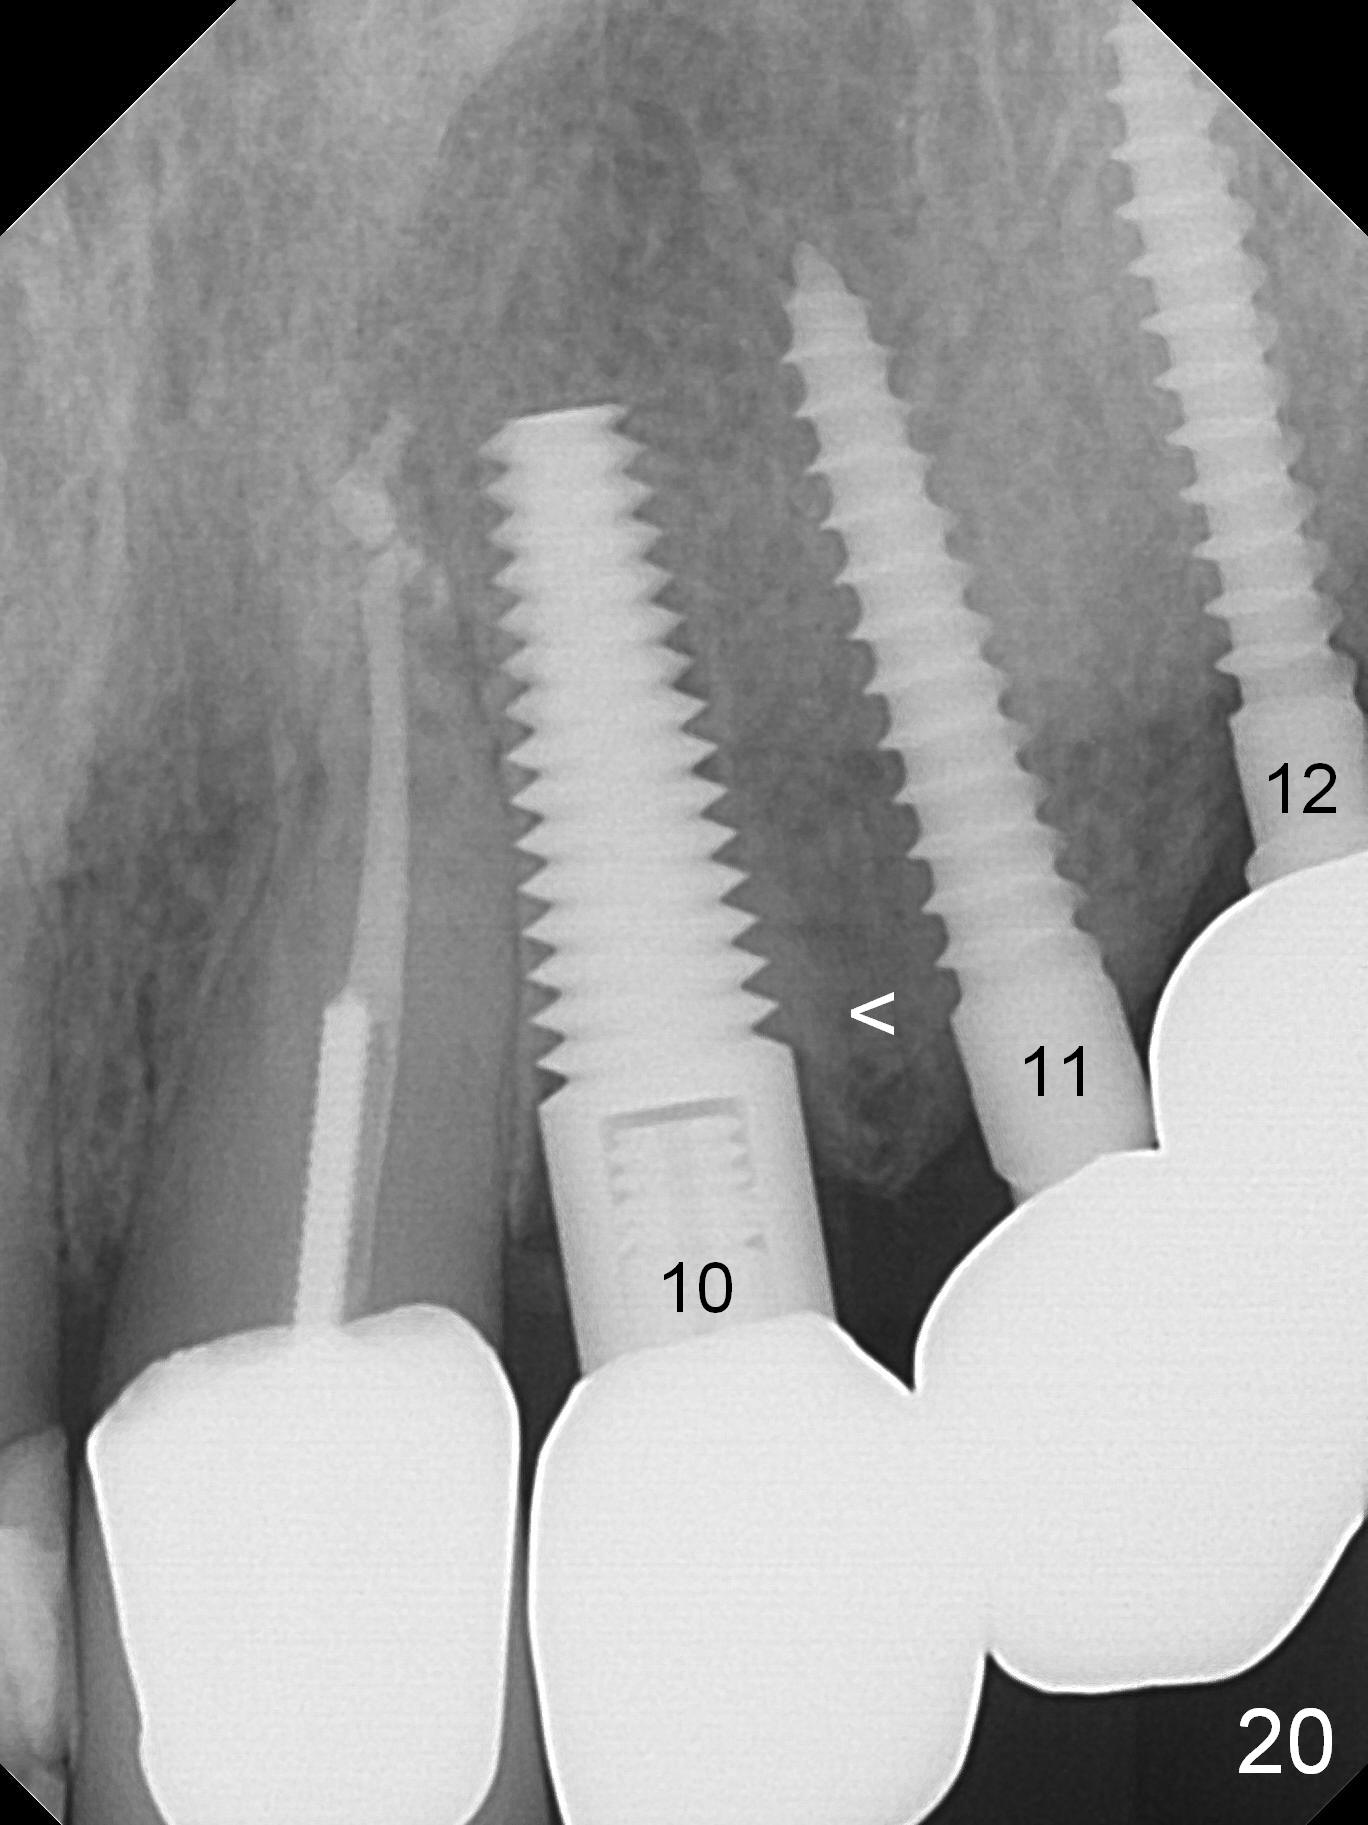

Six months post cementation, the tooth #9 becomes symptomatic. Is it possible that the implant at #10 is too close to the root of #9? It is asymptomatic after pulpotomy, but the tooth fractures equi/supragingivally. Two PAs taken while RCT show osteointegration at #10-12 (Fig.18,19). While the bone density increases at #10 regular implant, there is minimal bone loss around the 1-piece implants 13 months post cementation (18 months postop, Fig.20,21). The gingiva remains healthy 19 months post cementation (Fig.22). 76岁病人突然打电话说一个植牙牙冠松动,其实9号牙(自然牙)折裂,6,10-13号牙植牙好像没有骨质吸收(图二十三至二十五),10-13牙位牙龈健康(图二十六,行使功能五年)。9号牙牙冠重新粘固后,显示前牙深覆合,深覆盖(图二十七,二十八)。如果再次脱落需要植牙,选择一段式有助于植入和修复,因为植体和基台直径小。两段式植牙相对基台直径至少4,或者4.5毫米,前牙修复显得笨重。由于9,10牙根和植体接近,9号牙植体需要偏小而长,3x14或者15毫米(图二十九)。